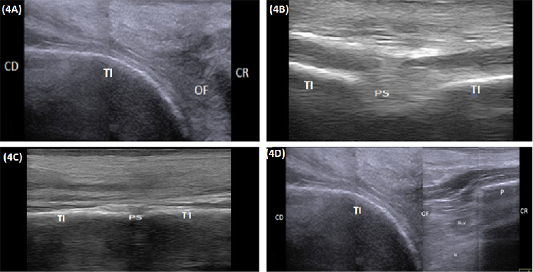

(A) Compound longitudinal sonogram (10 MHz linear rectal probe, 5cm depth) in a 7-year-old cow showing tabula of the ischium (TI), obturator foramen (OF), cranial direction (CR) and caudal direction (CD). (B) Transverse sonogram (10 MHz linear rectal probe, 5cm depth) of the caudal half of the pelvic floor in of the same animal in Figure: 4A showing the pelvic symphysis (PS) and tabula of the ischium (TI). (C) Transverse sonogram (10 MHz linear rectal probe, 5cm depth) of the cranial half of the pelvic floor of the same animal in Figure: 4A showing the pelvic symphysis (PS) and tabula of the ischium (TI). (D) Compound longitudinal sonogram (10 MHz linear rectal probe, 10cm depth) of the of the same animal in Figure 4A showing obturator foramen(OF), blood vessels (BL. V), nerve (N), tabula of the ischium (TI), pubis (P), caudal direction (CD) and cranial direction (CR).